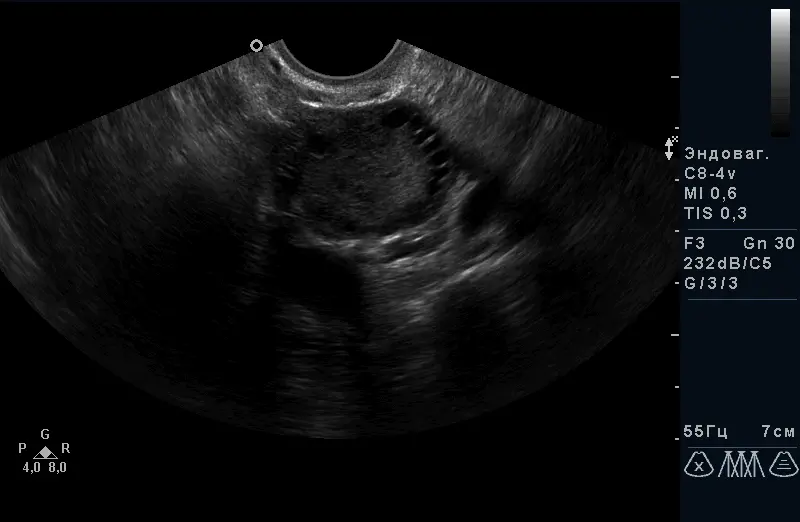

- Кісти яєчників

- Фолікулярний апарат яєчників

Трансвагінальний доступ є “золотим стандартом” в дослідженні органів малого таза на увазі найкращою візуалізації з найтоншої оцінкою структури, оптимальний метод в діагностиці вагітності на ранніх термінах, оцінці будови плода до 14 тижнів. Датчик розташовується в піхві.

За допомогою УЗД можна побачити і оцінити стан тіла матки, шийки матки, яєчників, маткових труб (при їх патології) і оточуючих їх органів. Є пріоритетним методом дослідження стану судин малого таза. Під час дослідження вимірюються розміри всіх доступних для дослідження органів, оцінюється їх структура і відповідність фазі менструального циклу, оцінка кровопостачання органів і судин.